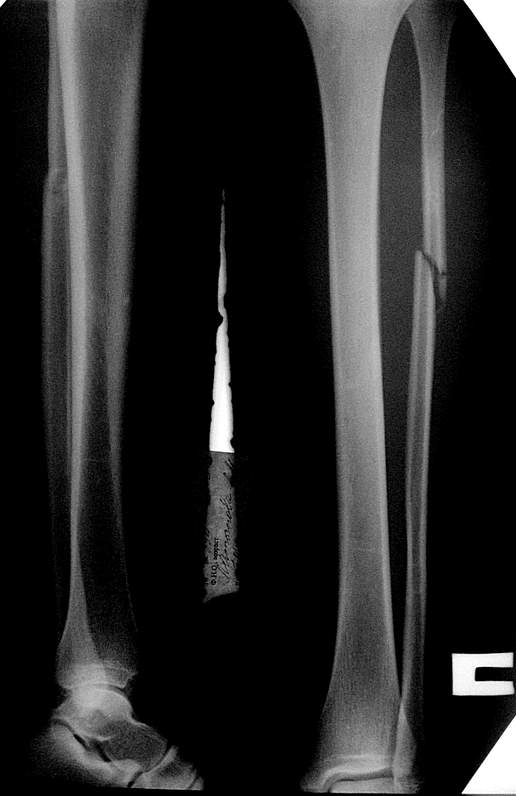

здесь пропускаем повреждение Maisonneuve...

Здесь как раз тот случай, когда рентгеновский снимок скрывает главную проблему. "Ходит, прихрамывая на правую ногу, отмечает боли в правом голеностопном суставе" По описанию клиника типичная для повреждения голонестопного сустава - синдесмоза.

При проксимальных переломах малоберцовой автоматически необходимо подозревать повреждение синдесмоза - Maisonneuve Fracture.

"На западе", как правило, при переломах голеностопа требуются снимки проксимальной части голени.

Описанное в 1840 году Maisonneuve повреждение характеризуется тем, что при фиксированной наружной ротации стопы повреждается передняя фибуло-тибиальная связка, часть синдесмоза, с переломом медиальной лодыжки и без, дальше разрыв продолжается по межкостной мембране и спиральный или косой перелом малоберцовой происходит выше.